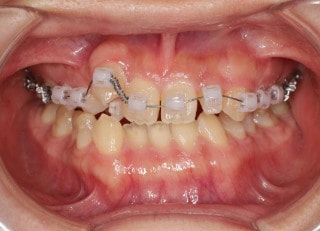

治療開始時